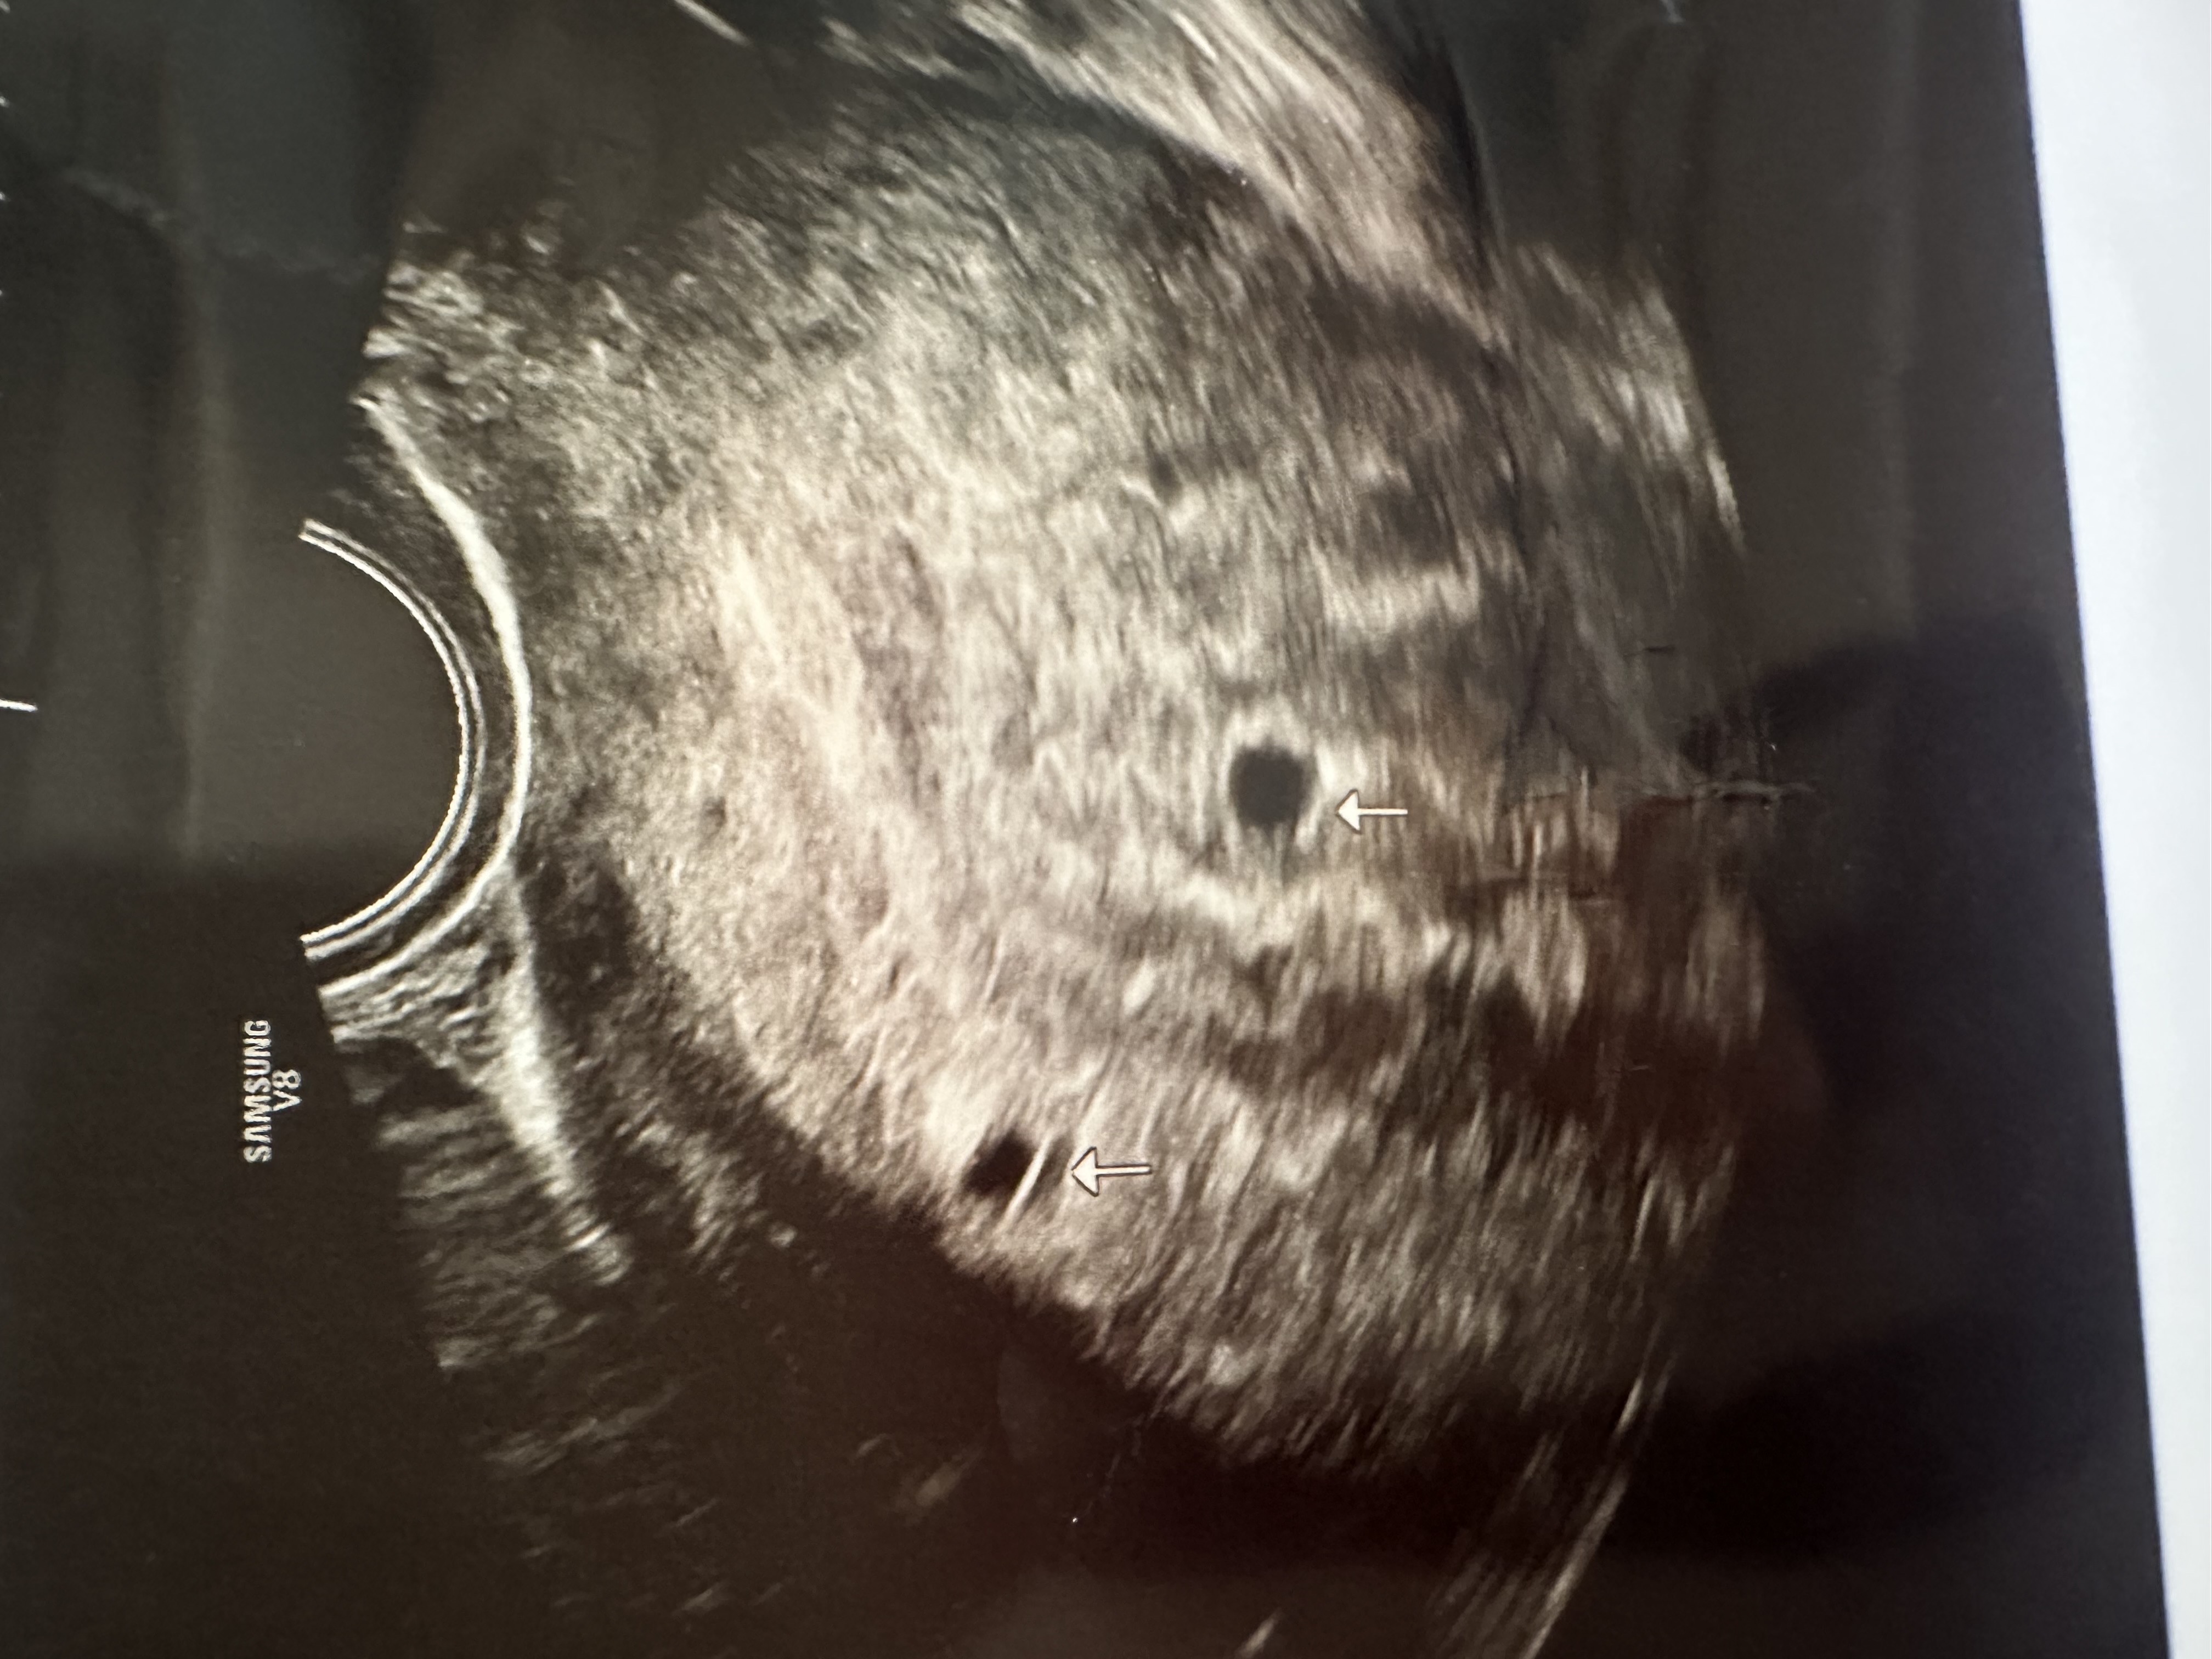

쌍둥이 맞을까요..?

오늘 촘파찍고왔는데 딱 5주라고 하셨고, 아기집 두 개가 보인다고, 담주에와서 다시 한번 더 보자하셨는데,, 이러다 하나가 소실될수도있다고 하셔서 별로 큰 기대는 안하고있지만 괜시리 걱정+설렘 왔다갔다하네요;;